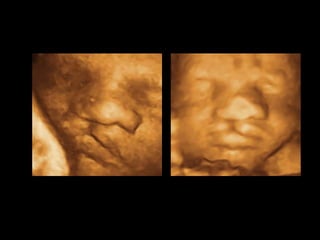

Ultrasound scan diagnosis

Ultrasound images of clefts of the lip can be visualized as

early as 16 weeks

• 15.

Ultrasound scan diagnosis Ultrasoundimages of clefts of the lip can be visualized as early as 16 weeks